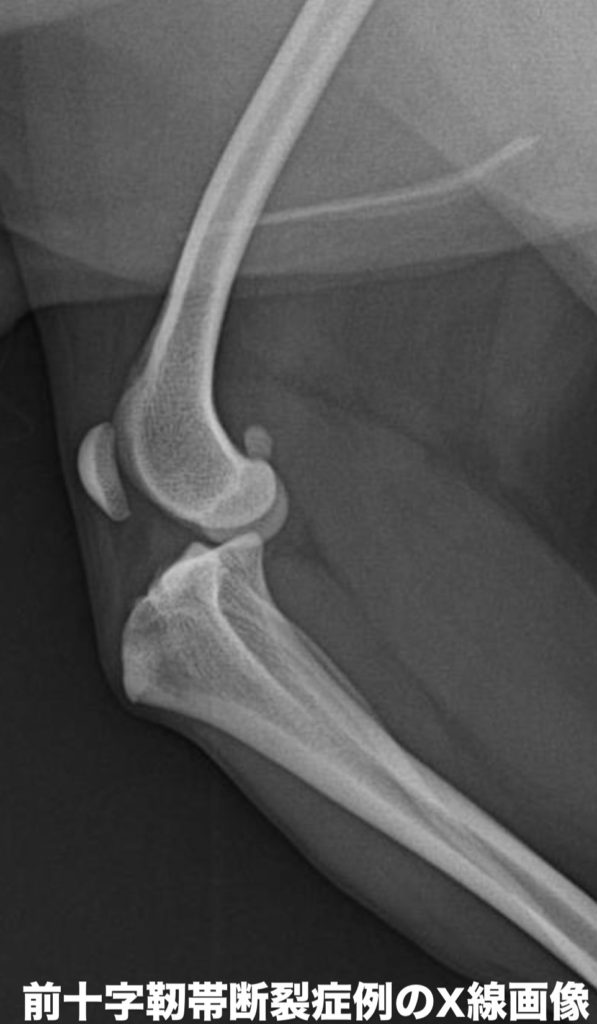

診断は、触診(脛⾻前⽅引き出し試験・脛⾻圧迫試験)による膝関節の不安定性の評価に加えて、X 線検査による⾻の位置や fat pad sign(関節内の炎症所⾒)の確認が基本です。

必要に応じて、超⾳波検査や関節鏡検査を併⽤することもあります。